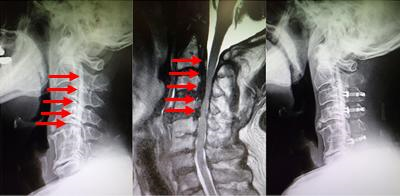

図 頚椎後縦靭帯骨化症

(左)術前レントゲン:椎体後方に後縦靭帯の骨化があります。

(まん中)術前MRI:骨化により脊髄が強く圧迫されています。

(右)術後レントゲン:椎弓が開き、脊柱管が拡大し、神経の通り道が拡大しています。